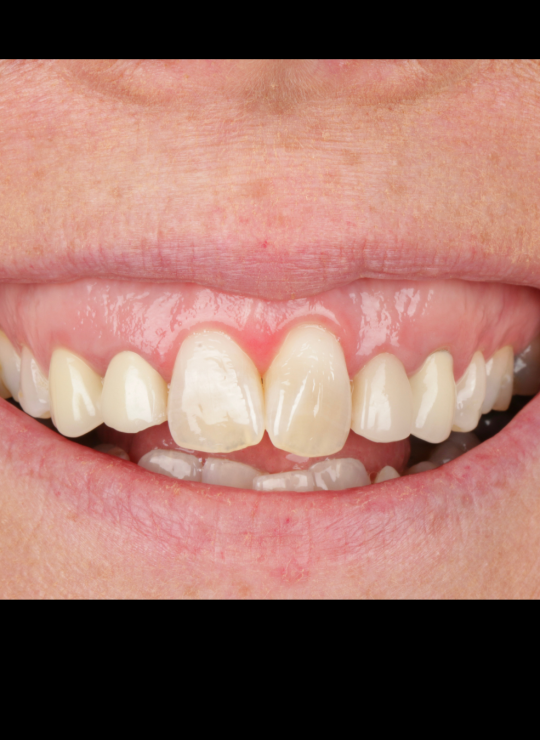

A Crown Lengthening Masterclass

Tailored for general dentists and specialists aiming to enhance expertise in crown lengthening. Ideal for those committed to elevating restorative dentistry and delivering predictable, high-quality outcomes for patients.

Case demonstrations: gummy smile correction, uneven gingival margins, anterior restorative integration (veneers, crowns)